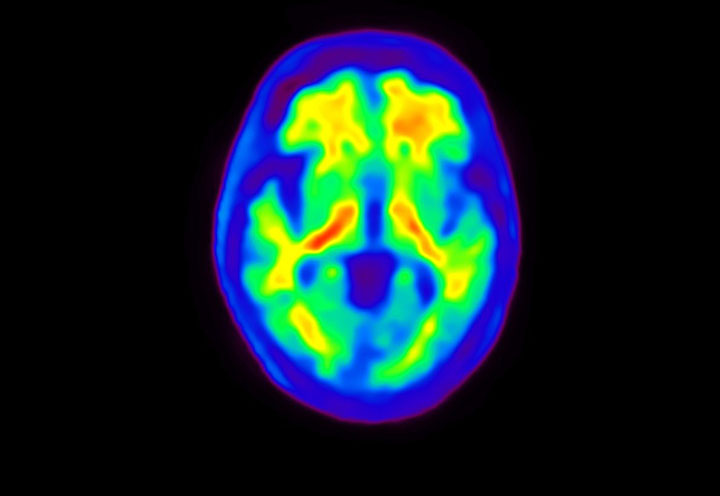

Head / Case4 : Amyloid

Coronal

Courtesy : Kindai University Hospital

- Imaging protocol

- Injected dose: 3.21 MBq/kg, 18F-Flutemetamol

- Uptake time: 100 minutes

- Scan time: 20 minutes